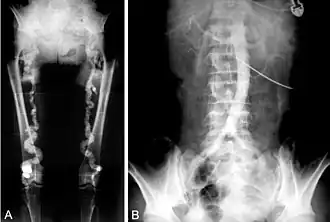

- Monckeberg's arteriosclerosis or medial calcific sclerosis is seen mostly in the elderly, commonly in arteries of the extremities.[10]